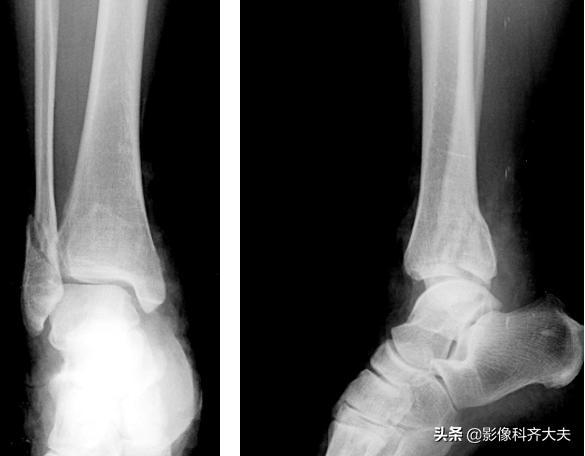

骨缺血性坏死:

骨折可使骨的一端血液供应障碍而发生缺血坏死。多见于股骨颈、腕舟骨及距骨骨折等。

左股骨颈骨折后股骨头缺血坏死 ,左股骨颈陈旧骨折,左股骨头变扁,碎裂,其内可见大小不等的囊状透光区